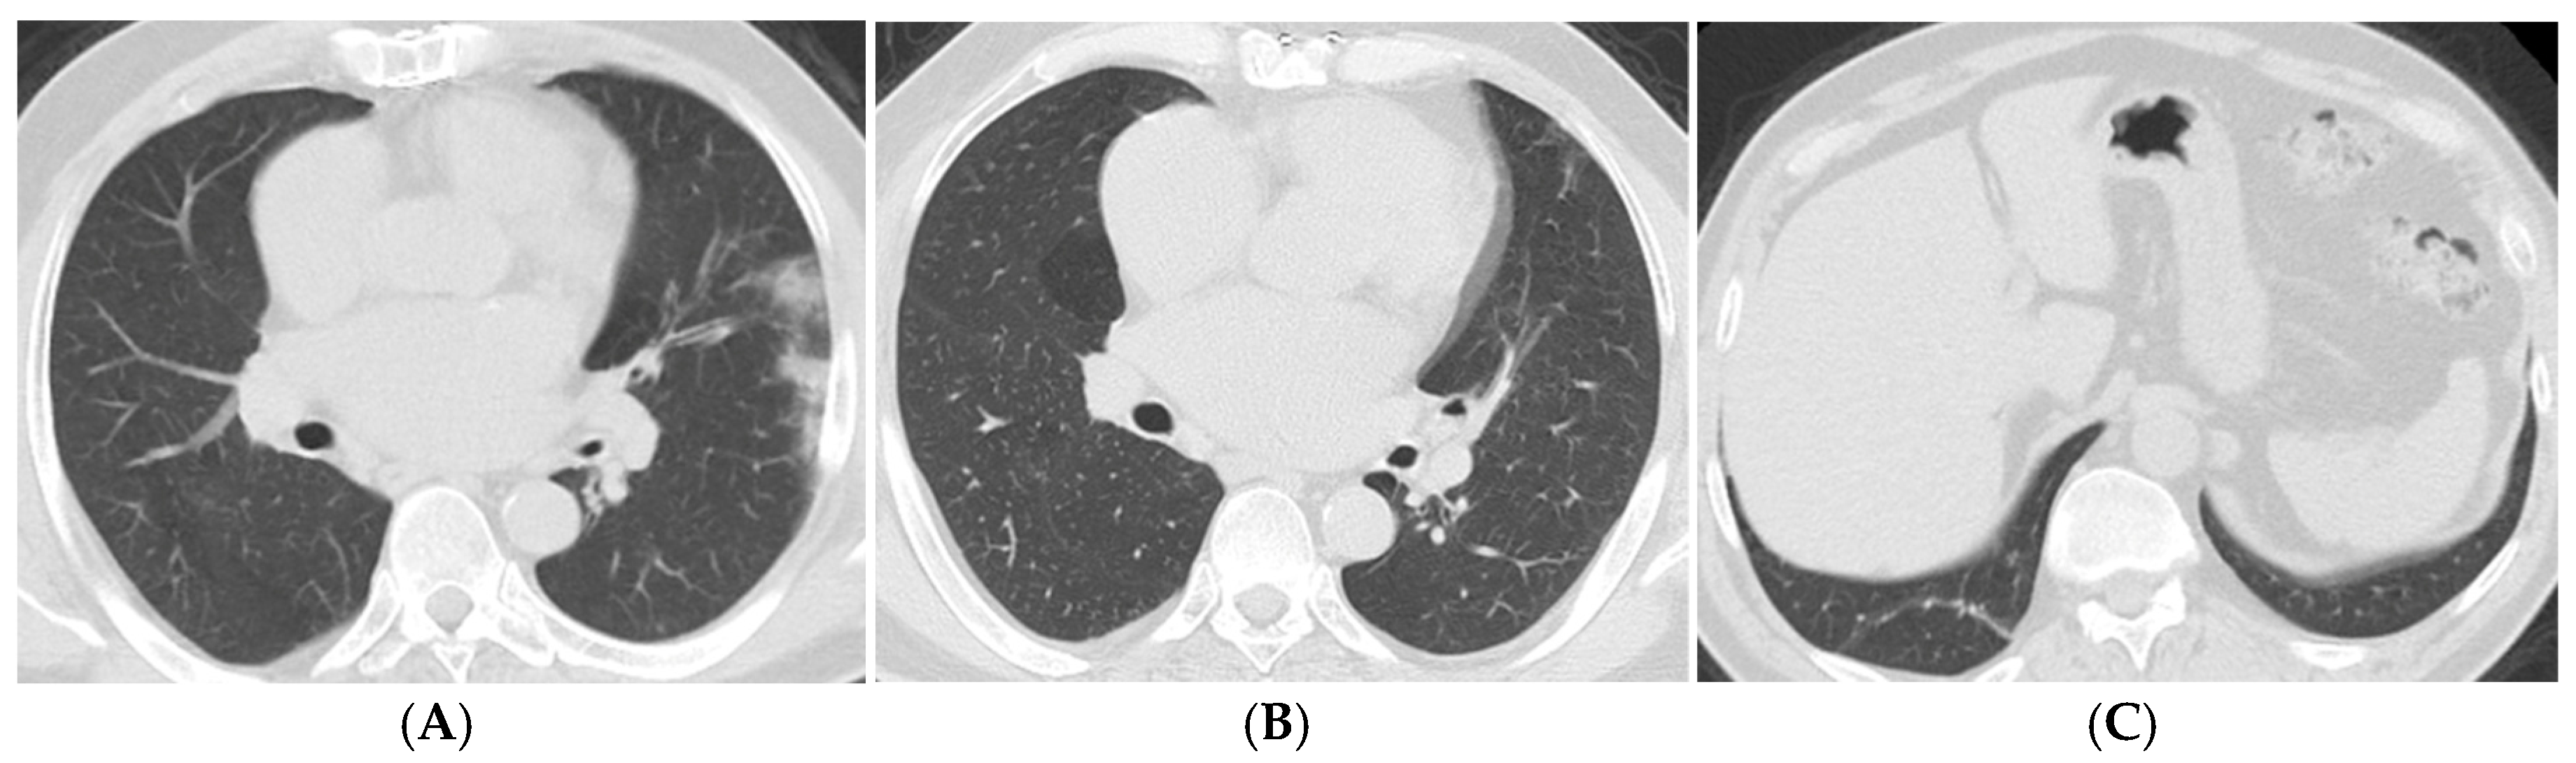

| Imaging Findings (>12 Months) | Common Findings | Persistent fibrotic changes, cysts, ground-glass opacities |